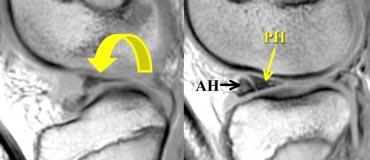

Bên trái là các hình ảnh PD sagittal của một trường hợp sụn chêm lật.

Toàn bộ sừng sau bị lật ra phía trước, tạo ra dấu hiệu sụn chêm rỗng (empty meniscus sign) (mũi tên).